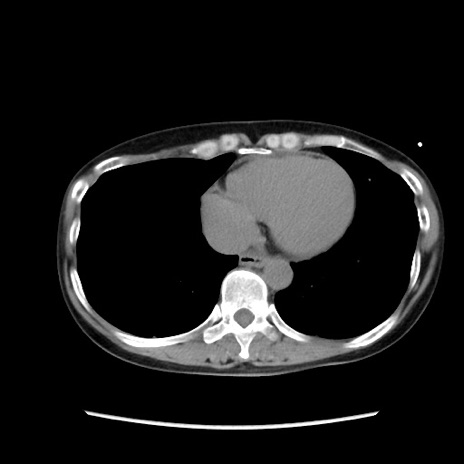

症例32(横断像)

【症例】40歳代 女性

【主訴】上腹部痛、嘔気・嘔吐

【現病歴】約9時間前頃から急に上腹部痛、嘔気、嘔吐が出現。改善しないため救急要請。

【既往歴】子宮頚癌(広汎子宮全摘術、放射線療法)、腸閉塞

【身体所見】腹部:平坦、軟、腸雑音亢進、上腹部を中心に腹部全体に圧痛あり。

【データ】WBC 8400、CRP 0.03